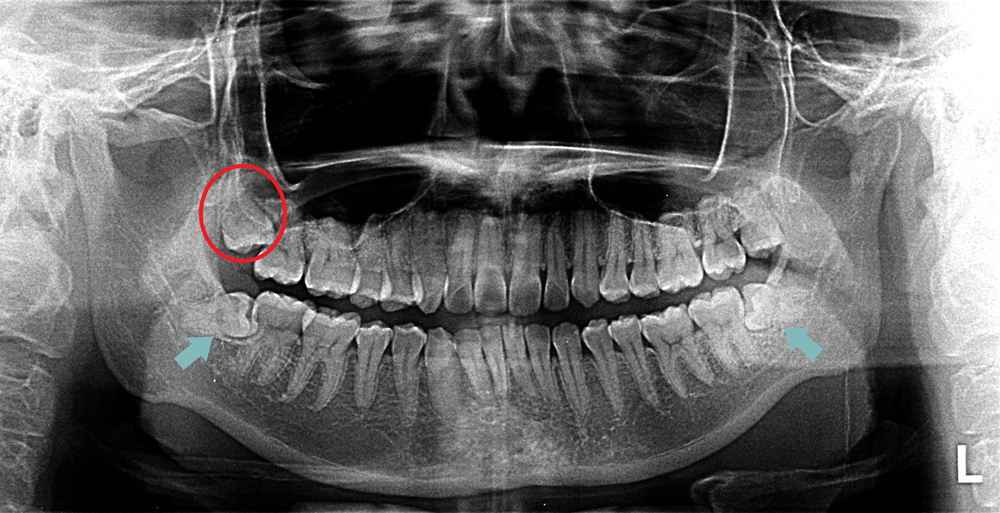

impacted wisdom tooth xray Impacted ray diagnosis

Impacted Wisdom Teeth X Ray Photos - TeethWalls

teethwalls.blogspot.comimpacted ray diagnosis

teethwalls.blogspot.comimpacted ray diagnosis